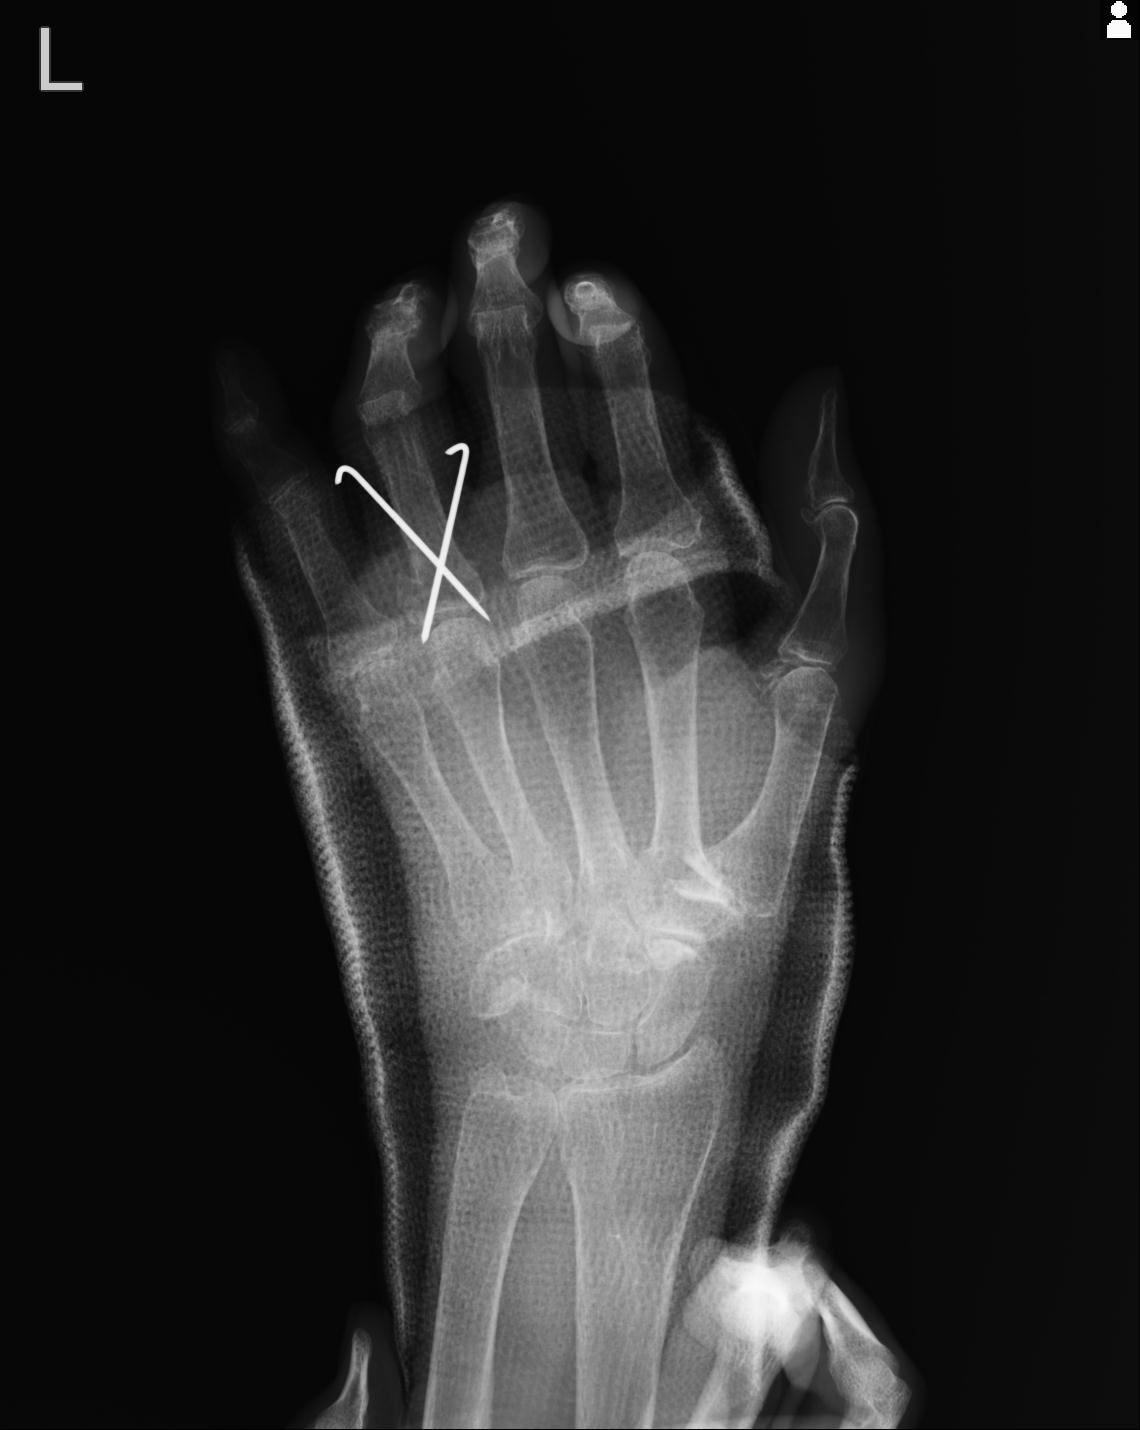

20857 1/11 左手 3R 1/19 4R 55歳男性 小指中節骨骨折